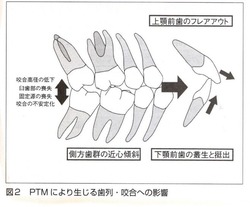

臼歯部が何らかの理由で近心部の歯を押し出していくメカニズムは上下ほぼ同じです。

下の図は歯の押し出しが前歯まで影響を与えている症例です。

大臼歯部が近心に傾いて咬み合わせの高さが低くなるとその歪みが前歯に伝わり、前突状態となります。